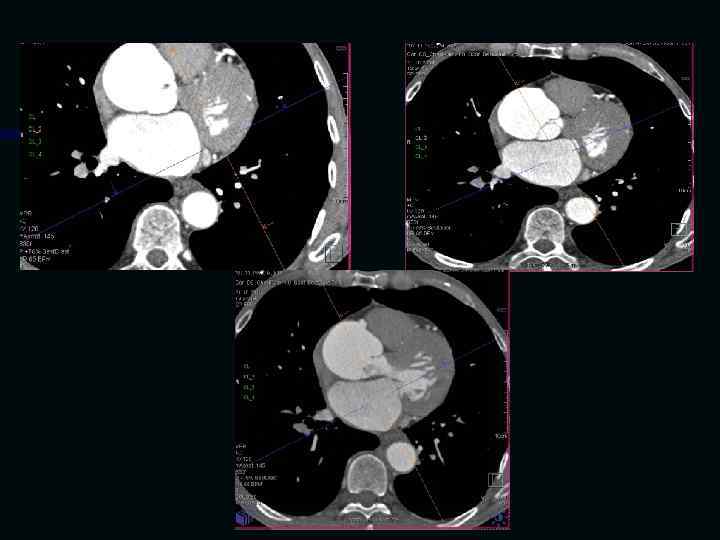

Исследование сосудов грудной клетки